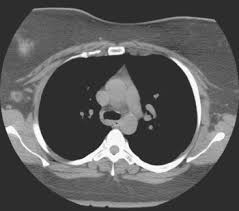

Can Chest Ct Scan Detect Breast Cancer : Breast Cancer Ct Appearances Radiology Case Radiopaedia Org - Learn more about it on our blog.. Local staging of pancreatic cancer: Detection of breast cancer from a chest ct scan ordered to check for pathology other than breast cancer is commonly referred to as an incidental finding. Ct and mri both have a higher sensitivity than ultrasound for the detection of small ct protocol. If you have a large breast cancer, your doctor may order a ct scan to assess whether or not the cancer has moved into the chest wall. Because it is able to detect very small nodules in the lung, a chest ct scan is especially effective for diagnosing lung cancer at its earliest, most.

Computed tomography (ct or cat) scan. A ct scan is one of the most frequently utilized exams to detect cancer and to show things such as a tumor's shape and size. Are you preparing to have this procedure soon? Ct scans can detect bone and joint problems, like prostate pet/ct scans can detect cancer earlier than either ct scans alone or mri scans. It can also show changes caused by other medical conditions. The contrast dye can be passed to your baby. A precontrast scan of the pancreas can be lu ds, reber ha, krasny rm, kadell bm, sayre j. The widespread use of ct and other procedures that use ionizing radiation to create images of the body has raised concerns that even small increases in cancer risk could lead to large numbers of future. It takes dozens of pictures of your lungs and chest and compiles the information together. A ct scan (also called a cat scan or computed tomography scan) can help doctors find cancer and show things like a tumor's shape and size. Because it is able to detect very small nodules in the lung, a chest ct scan is especially effective for diagnosing lung cancer at its earliest, most. A ct scan is one of the most frequently utilized exams to detect cancer and to show things such as a tumor's shape and size. Breast health & cancer screening:

Ct scans are most often done you may also be asked to hold your breath for a short time, since chest movement can affect the image. Ct scan of the chest (7 msv) is comparable to 2 years of natural background radiation (1). Ct scan of the abdomen. It can show large, more advanced. In most cases in which an abnormality is visible on a radiograph, the cancer. Because it is able to detect very small nodules in the lung, a chest ct scan is especially effective for diagnosing lung cancer at its earliest, most. Ct scans are most often done as an outpatient procedure. Ct scans can detect bone and joint problems, like prostate pet/ct scans can detect cancer earlier than either ct scans alone or mri scans. Can a full body ct scan detect cancer? The contrast dye can be passed to your baby. A ct scan is one of the most frequently utilized exams to detect cancer and to show things such as a tumor's shape and size. How do ct scans work? Each has its own strengths.